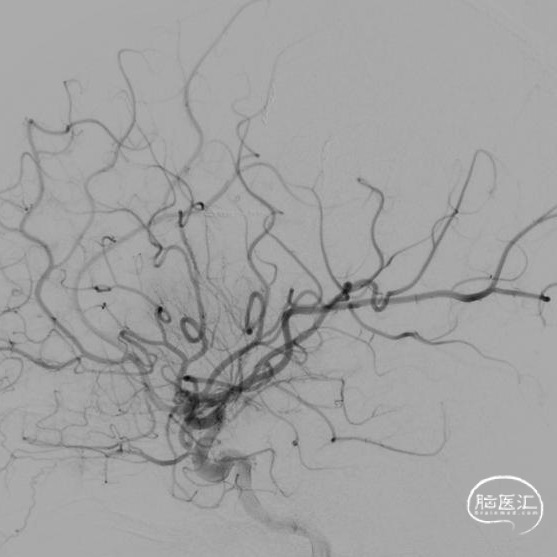

本例患儿肿瘤位于双侧额顶叶,大脑镰旁,增强扫描呈明显环形强化,提示肿瘤血运丰富。患儿年龄小,体重低,相对血容量少,如何控制术中出血是手术成功的关键。而术后肢体瘫痪或瘫痪加重是手术的主要并发症,中央沟静脉损伤、胼周动脉损伤、中央沟局部皮层损伤、癫痫、血肿以及脑水肿加重是其常见原因。术前脑血管造影有助于判断肿瘤与周围血管、组织的位置关系,明确上失状窦有无闭塞,对手术的切口设计有重要的参考价值及避免术中损伤不易发现的血管及组织。

本例患者术前脑血管造影提示瘤体主要由双侧大脑前动脉终末分支供血,造影静脉期瘤体显影明显,因此我们选择先采用神经介入技术超选部分主要供瘤动脉予弹簧圈栓塞,减少瘤体的供血。之后再行开颅探查双侧额顶叶占位性病变切除术。

儿童颅内肿瘤多血运丰富,且儿童本身体重低,血容量较少,开颅术中对于出血的控制尤为关键。术前尽可能的明确肿瘤与周围血管、组织间的关系,切口设计既要能够安全、彻底地切除肿瘤,又要避免无效开颅和无效脑暴露,增加不必要的医源性创伤,不可过分强调小骨窗,当肿瘤血运丰富,有条件时尽可能行供瘤血管栓塞,减少术中切肿瘤时出血。